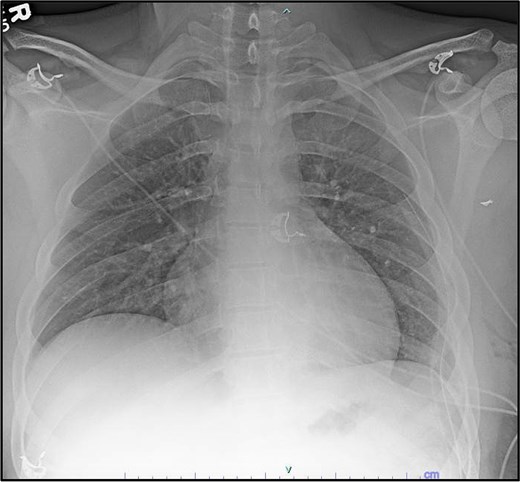

The patient was discharged on post-operative Day 1 following chest tube removal with minimal output and no air leak; his discharge was Day 7 following the initial injury and admission. He was stable without acute concerns and was discharged home. At his 2 week follow-up, he was doing well without pain or shortness of breath (Fig. 6).